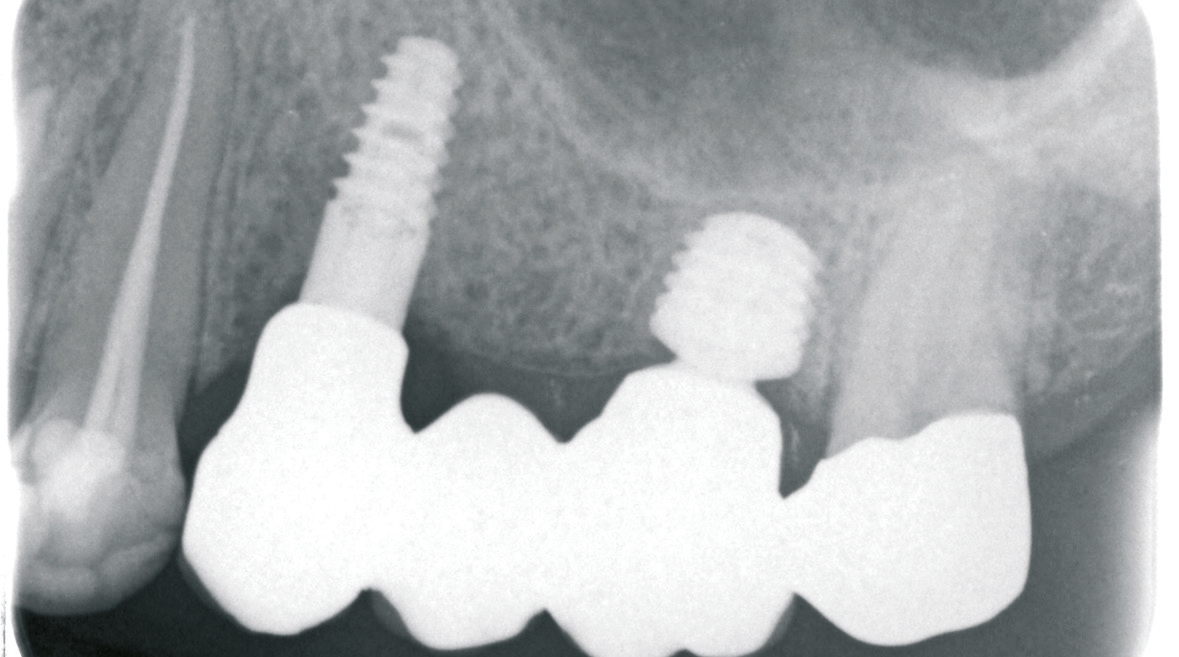

Beim Fehlen von mehreren Zähnen können unterschiedliche Planungs- und Versorgungskonzepte zur Anwendung kommen. Zur Kompensation der geringeren Verankerungsfläche von kurzen Implantaten im Knochen wird neben der Zahn-für-Zahn-Versorgung eine Verblockung von multiplen Implantaten empfohlen [6]. Die Empfehlungen sind aber im Kontext der jeweiligen Implantat- Aufbau-Verbindung, die bei der Versorgung von kurzen Implantaten zur Anwendung gekommen ist, zu berücksichtigen. Aus dem Anwendungsbereich der Implantate mit einer externen Implantataufbauverbindung wird eine Verblockung angeraten, um eine ausreichende Stabilität besonders bei einer hohen Aufbauhöhe des Zahnersatzes sicher zu stellen [6]. Die Erfahrung bei der Anwendung von Implantaten mit einer konischen Implantataufbauverbindung hat gezeigt, dass sich multiple Einzelkronen langzeitstabil eingliedern lassen [2] (Abb. 9-14). Besonders in Hinblick auf das periimplantäre Knochenniveau wird davon ausgegangen, dass sich bei der Einzelversorgung keine Spannungen auf Grund einer unzureichenden zahntechnischen Herstellungsgenauigkeit ergeben können.

Zeigt sich im Rahmen der Planung, dass das vertikale Knochenangebot nur in einem Bereich des zahnlosen Kieferkammabschnittes vorliegt, können kurze Implantate auch mit längeren Implantaten kombiniert werden. Dann kann anstelle der multiplen Einzelversorgung auch eine Brückenversorgung angegangen werden (Abb. 15-18). Bei der Verblockung von Implantaten mit einer konischen Implantataufbauverbindung muss auf eine genaue Übertragung der Implantatanschlussgeometrie geachtet werden, da es durch die Toleranzen bei der Herstellung des Konus zu einem vertikalen Versatz kommen kann. Im Vergleich zu Implantaten mit einer zylindrischen, parallelen Verbindung fehlt hier der Anschlag, der eine genaue Übertragung der vertikalen Position sicherstellt. Um diesen vertikalen Fehler zu vermeiden empfiehlt es sich auf Abutmentniveau abzuformen. In diesem Fall kann das Abutment auch in-situ verbleiben, so dass das periimplantäre Weichgewebe nicht mehrfach traumatisiert wird.